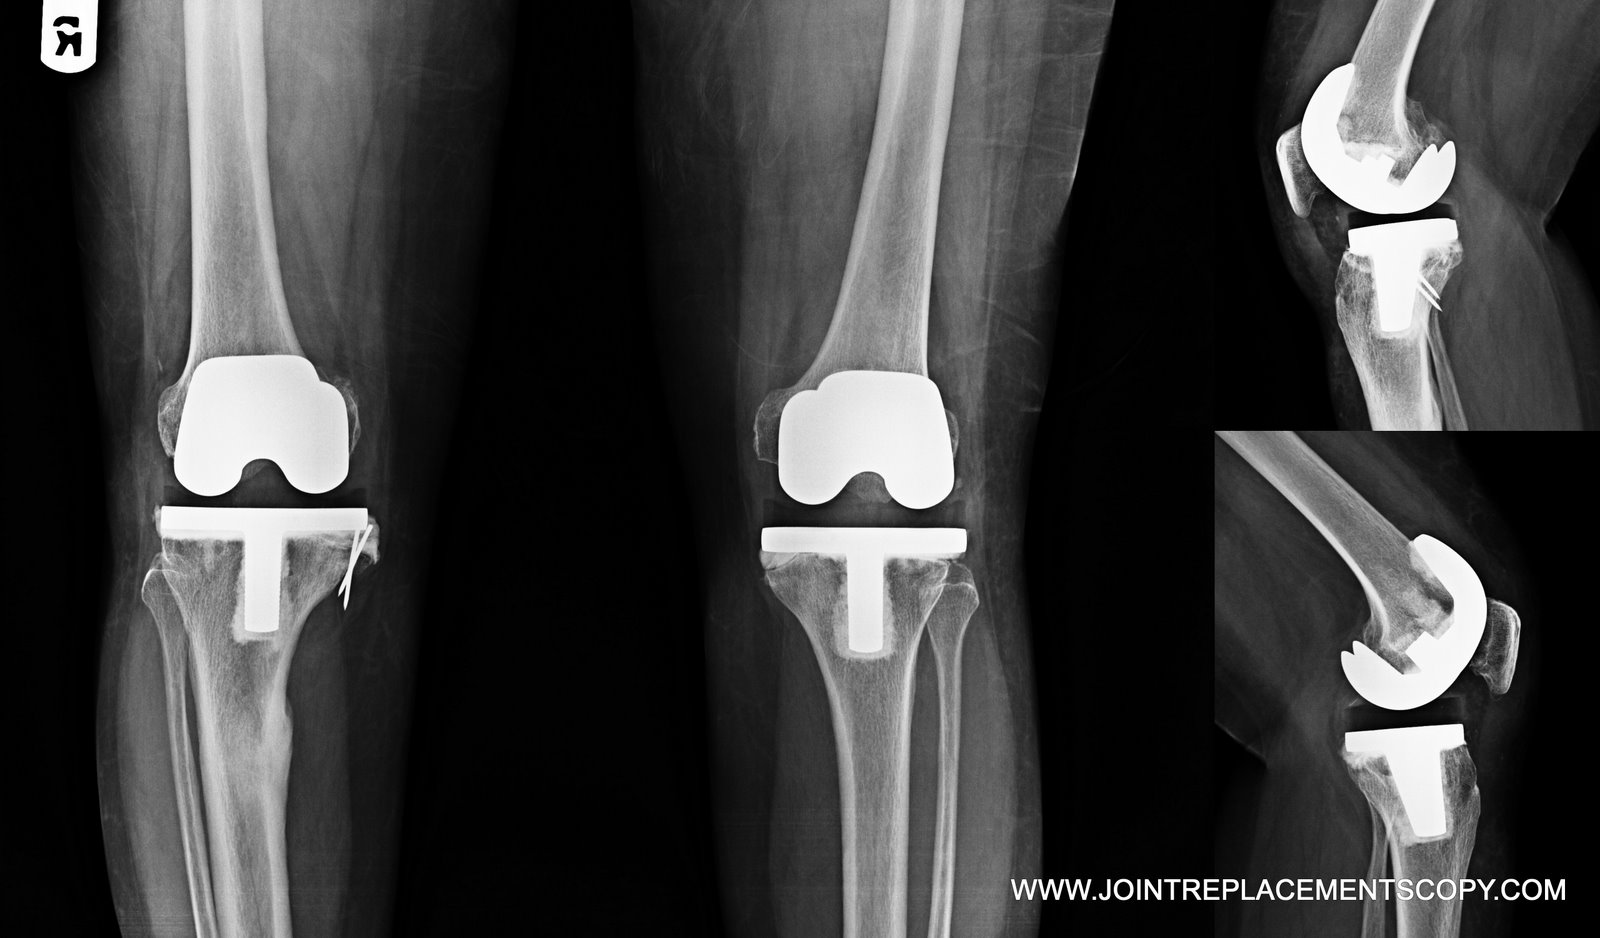

From jointreplacementscopy.blogspot.com

Jointreplacementscopy Knee joint replacement Female Knee Joint Replacement A minimally invasive surgery uses a smaller cut (incision) than a traditional total knee replacement. statistics from the american joint replacement registry underscore the vulnerability of the female knee: Knee replacement surgery is a safe and effective treatment for finding relief from the pain and swelling associated with knee osteoarthritis. Nearly 60% of knee replacements. knee replacement is. Female Knee Joint Replacement.

From www.researchgate.net

Female aged 74 y with bilateral knee joint replacement (patient N o... Download Scientific Diagram Female Knee Joint Replacement A minimally invasive surgery uses a smaller cut (incision) than a traditional total knee replacement. This type of surgery typically requires special tools so that the surgery team can see and do the procedure through the smaller incision. statistics from the american joint replacement registry underscore the vulnerability of the female knee: It’s a type of procedure called an. Female Knee Joint Replacement.